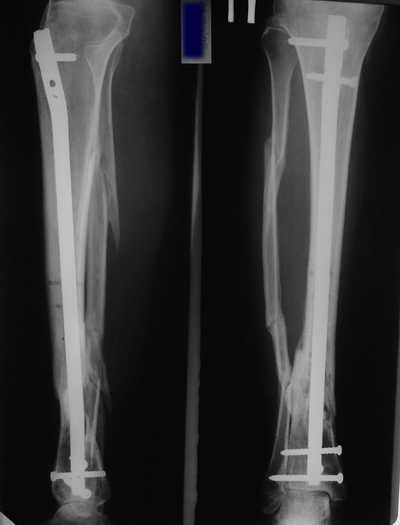

Male 54 years old, diabetic, blind in both eyes, with infected (MRSA) non union distal tibia after fracture 8 month ago. In acute phase treated by ORIF with LCP tibia and fibula. Treatment complicated by infection and after 6 month hardware was removed and treatment continued by cast fixation. You can see malposition of fragments In this stage beginning treated by Ilizarov fixation with use Hexapod system, allows anatomical position of fragments and you see signs of union.